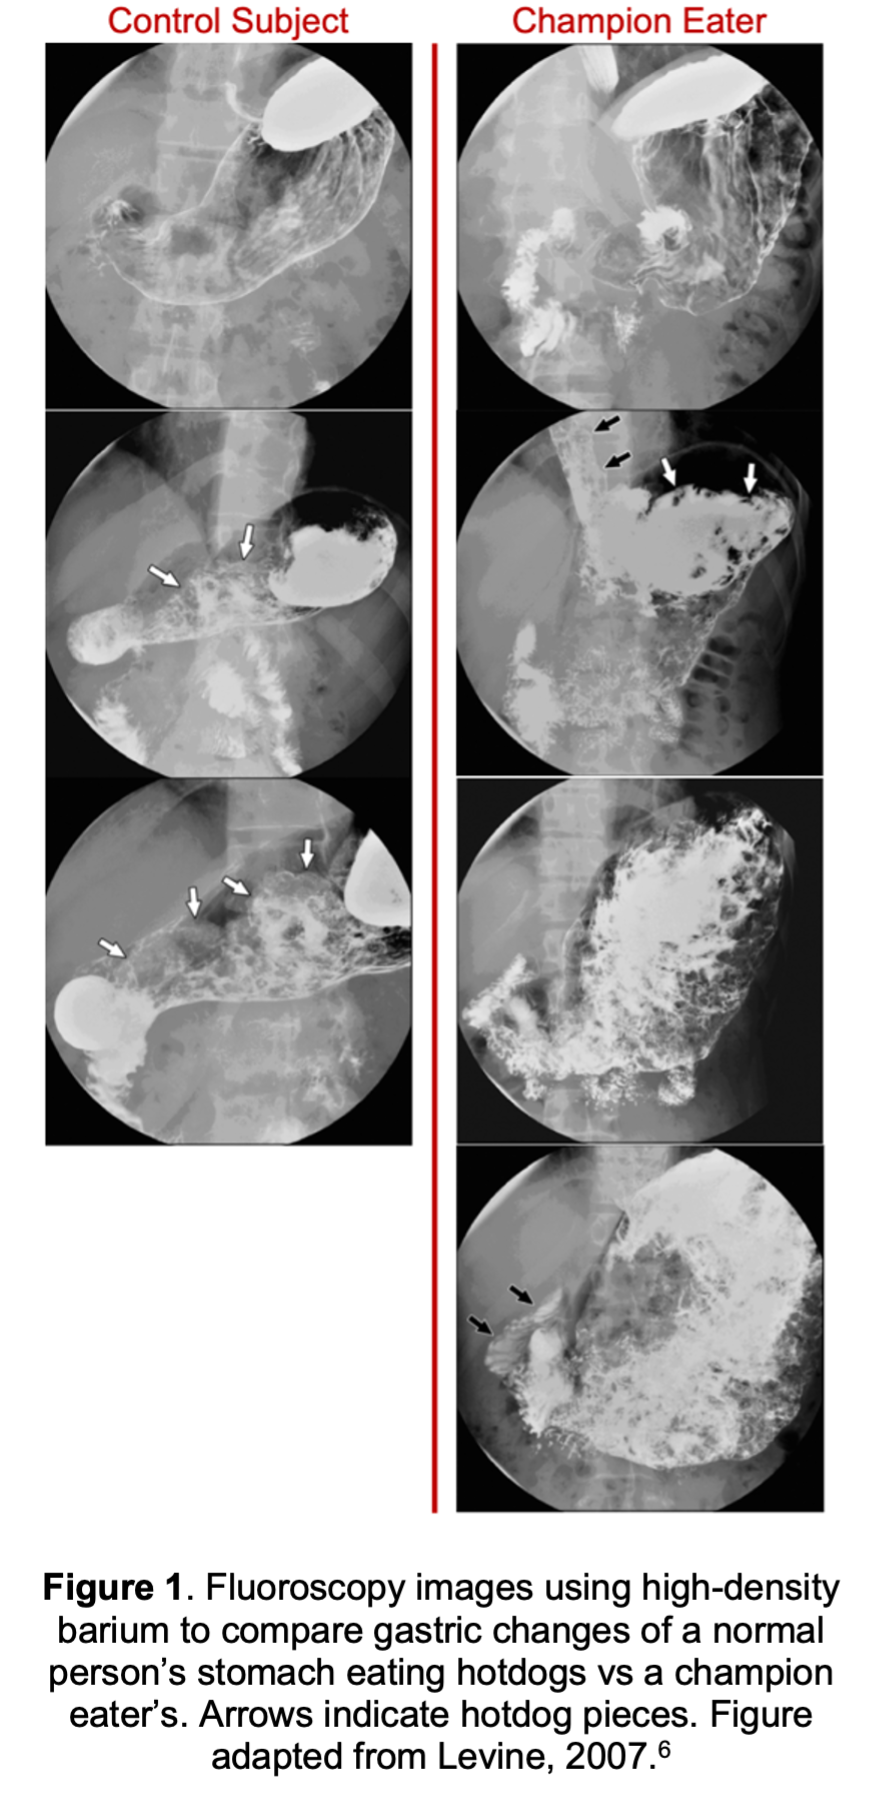

The stomach was one of the first organs to be studied with scientific stomach observations dating back to the 1500s1. The volume of the average empty human stomach is 45-75 mL, yet the stomach can expand during feeding to anywhere from 1.5 liters in lean adults, to 4 liters in those with binge eating disorders2–4. To visualize this, think of a flattened balloon sitting in your abdomen, then consider how big that balloon is when fully blown up! Your stomach can stretch to over five times its size because it is a smooth muscle tube5. Consider Joey Chestnut, who holds over 46 food eating records, including his record of eating 74 Nathan’s Famous hot dogs in 10 minutes. Figure 1 shows how much the human stomach can distend for competitive eaters who practice this stretching6.